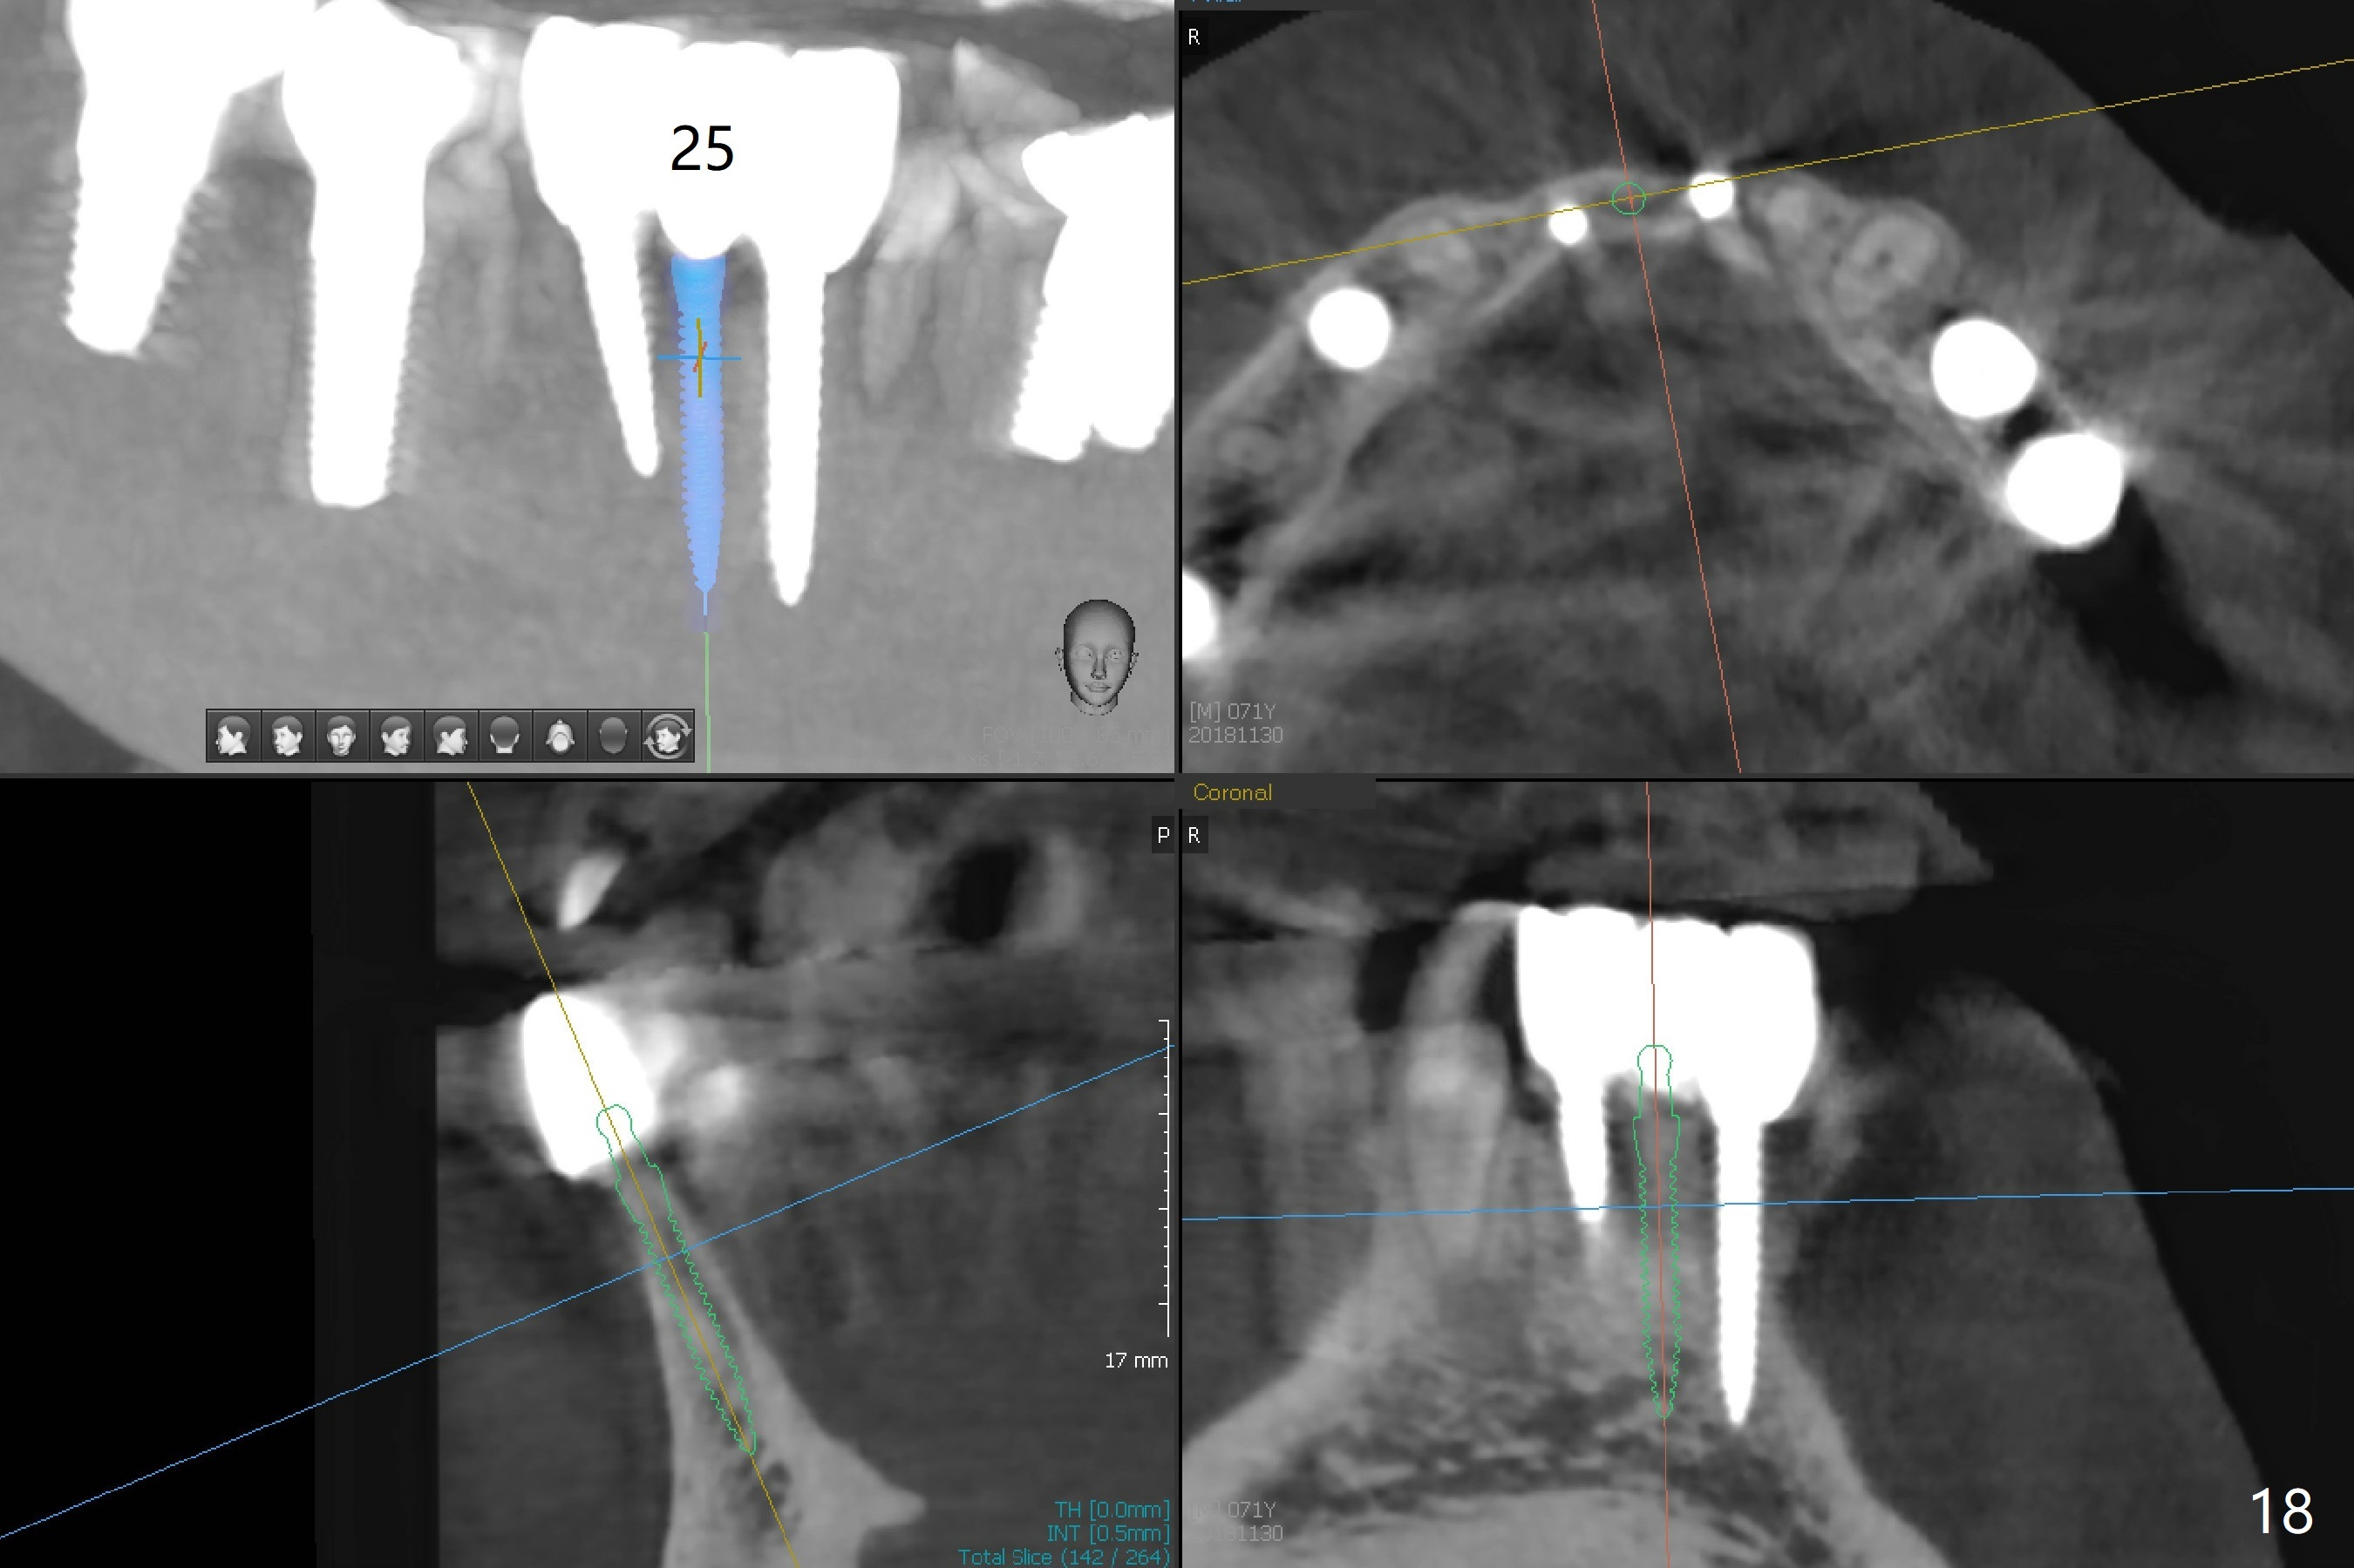

The infection persists at #26 four years 8 months post cementation (Fig.16 *). CBCT is taken. In fact the implant at #26 was placed lingual (Fig.17), while that at #24 buccal (Fig.20). The 2nd option is to remove the implant at #26 and place a 2 mm one at #25 (Fig.18,19). Fabricate a 3-unit cantilever FPD. Take 5x5 cm CT with 1.2 mm drill in place for 10 mm. Change the trajectory and position if necessary.